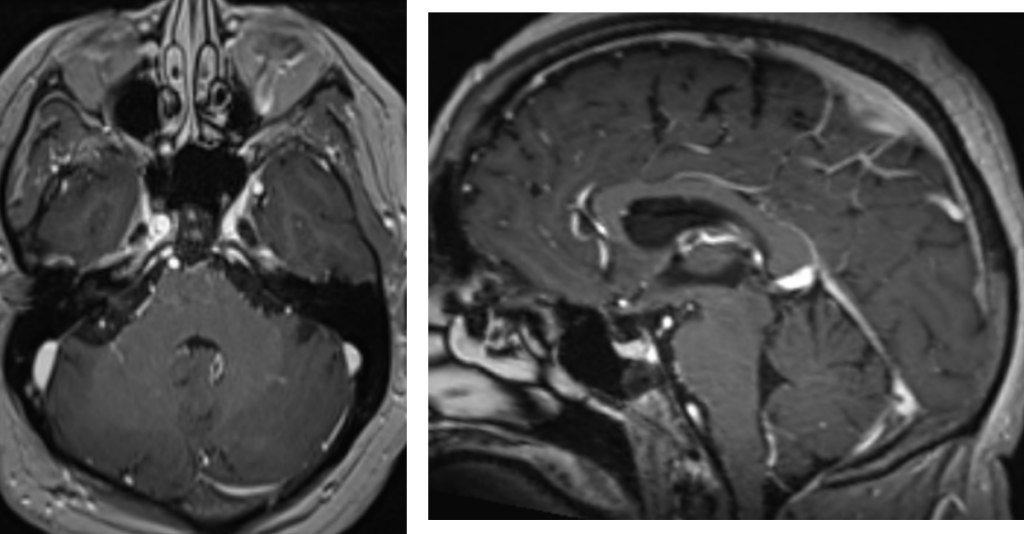

Figura 4: examinare IRM axial şi sagital T1 postcontrast

DE LUAT ACASĂ!!! Examenul IRM studiază semnalul leziunii cu o caracterizare tisulară optimă, evaluarea extensiei, ajută la orientarea diagnostică (perfuzie, difuzie, spectroRM, angioRM dinamic).

CT-ul poate fi util în analiza bazei craniului, detectarea calcificărilor şi pentru analiza anumitor structuri (pereţi orbitari, lama ciuruită etmoidală, găurile bazei craniului). Se poate realiza și în contraindicații de examen IRM.